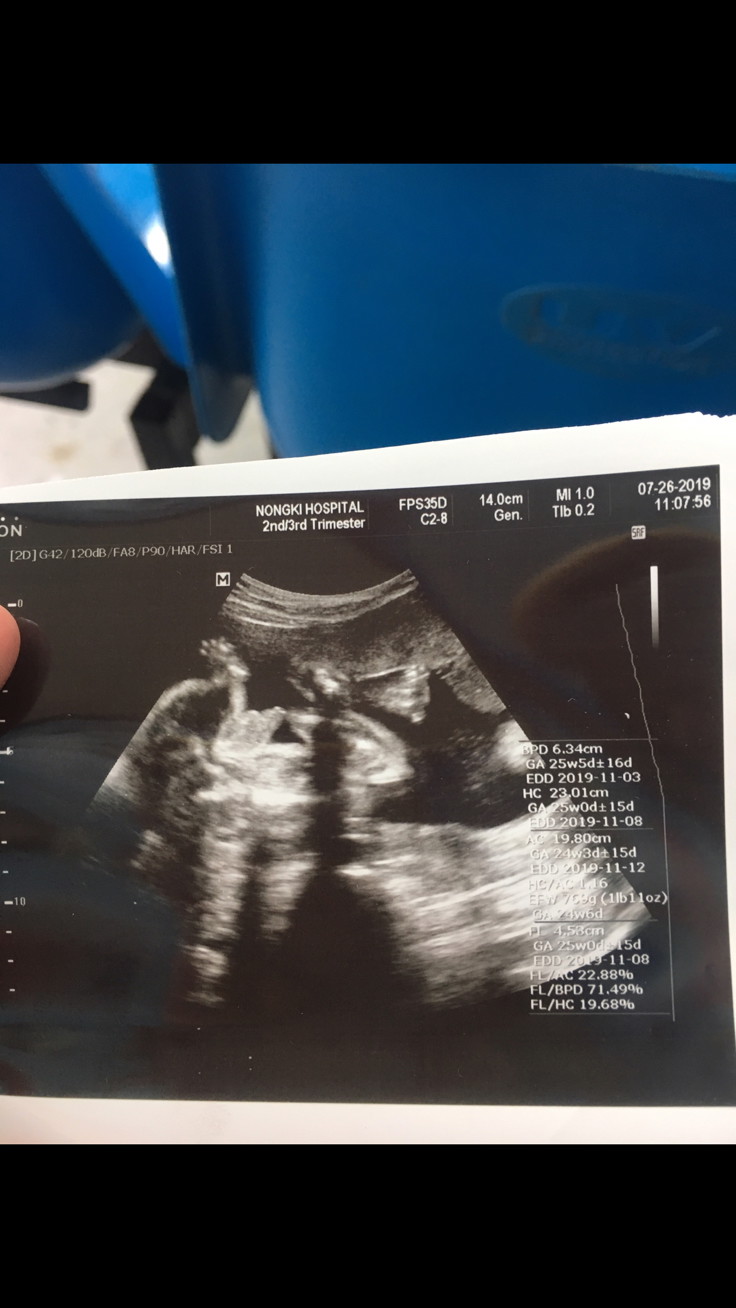

แม่ๆช่วยดูหน่อยค่ะว่า ญ หรือ ช

รบกวนแม่ๆช่วยดูน้องให้หน่อยค่ะว่าเพศไหน

ชายค่ะ

ชายคะ

ช ค่ะ

ชาย

จู๋ค่ะแม่